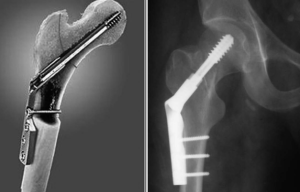

Скусывание выступающего отдела внутренней части выполняли непосредственно перед промыванием и послойным ушиванием парапателлярного доступа. Рентгеновский контроль целой конечности подтвердил корректное расположение телескопических стержней (рис. 2).

Демонтаж аппарата произведен под общей анестезией, титановые телескопические стержни оставлены in situ (рис. 7). На рентгенограммах после снятия отмечена корректная позиция телескопических стержней, адекватное удлинению их расхождение и сохранение фиксации резьбовых частей в эпифизах и апофизе большого вертела. Наложена дисциплинирующая гипсовая лонгета на 10 дней. Вертикализация с нагрузкой на конечность была разрешена на первый день после операции.